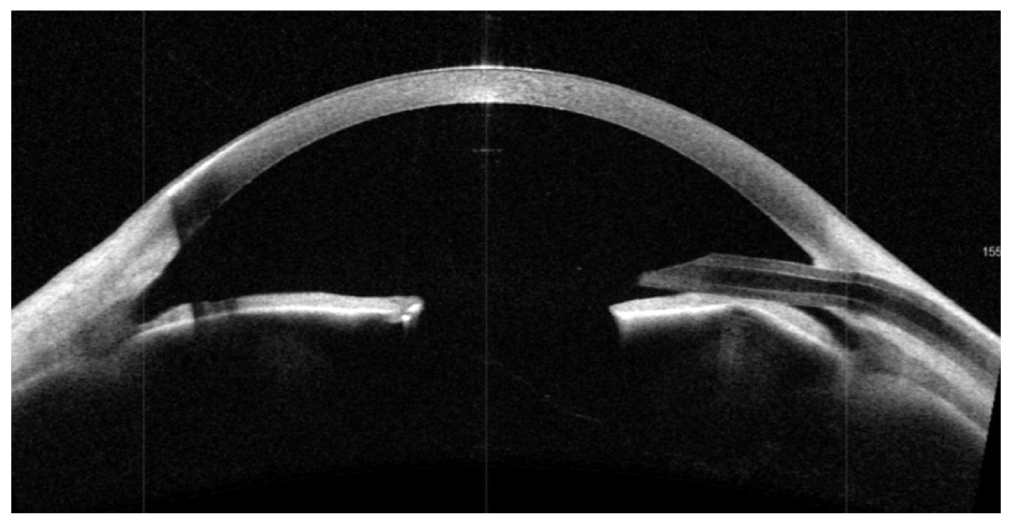

Оптическая когерентная томография переднего отрезка глаза. OD: в верхненаружном сегменте (на 11 часах) визуализируется трубка клапанного дренажа в правильном положении (рис. 6).

Рис. 6. Оптическая когерентная томография переднего отрезка правого глаза после операции

Fig. 6. Optical coherence tomography of the anterior segment of the right eye after surgery